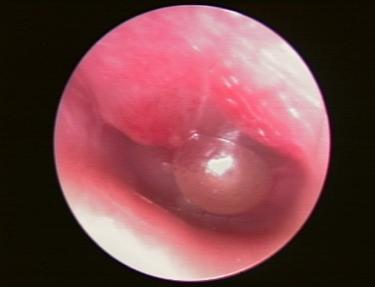

大皰性鼓膜炎又稱出血性大皰性鼓膜炎,是病毒感染引起的鼓膜和鄰近鼓膜的外耳道面板的急性炎症。

大皰性鼓膜炎在現代生活中較為常見,這個疾病多發於兒童和三十歲以下的人群,患有大皰性鼓膜炎往往會給患者的健康以及生活質量帶來一定影響,該疾病最主要的症狀就是耳部疼痛。如果有一天耳部突然發生疼痛並且迅速加重,那就有可能是得了大皰性鼓膜炎。此病首要症狀為外耳道劇痛,有時會伴有頭部疼痛的情況出現,在大皰破裂之後,耳部疼痛的情況則會逐漸減輕。

大皰性鼓膜炎患者的大皰破裂之後,患者的耳內會流出淡黃色或稀薄血液的分泌物,血皰破裂或自行吸收,在鼓膜表面一般不留痕跡或僅有鼓膜充血。大皰性鼓膜炎的患者會出現聽力下降,還會伴有耳部悶脹、耳鳴、眩暈、四肢無力、低熱等急性炎症的症狀表現,需儘快就診。

發現患有大皰性鼓膜炎患者要特別重視,需要立即到正規醫院的耳鼻喉科進行檢查,根據感冒病史、劇烈耳痛等症狀,加耳鏡檢查見大皰,可協助診斷。大皰性鼓膜炎還需要與急性化膿性中耳炎等疾病相鑑別。確診為大皰性鼓膜炎需積極治療,如果患者疼痛的情況較為嚴重需要進行鎮靜藥物治療,口服抗病毒藥物,區域性外用滴耳液,但選擇何種治療方法要聽從專業醫生的意見。